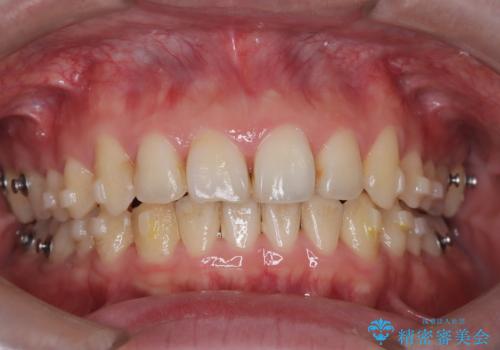

- 前歯が出ていることを主訴に来院されました。

歯列の幅が狭かったため、横に広げながらスペースを作り、叢生の改善を行いました。

左側の犬歯関係も治療前より良い状態で治療を完了することができました。

今回は臼歯部の遠心移動を行うために2級ゴムを使用しています。